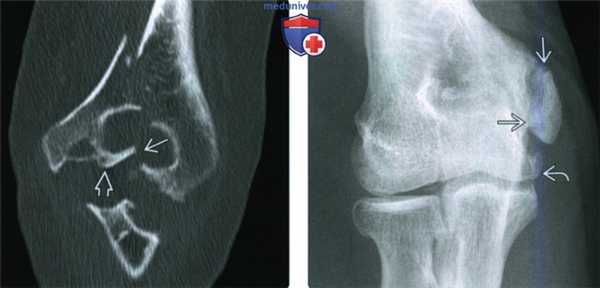

(Слева) На передне-задней рентгенограмме перелома медиального мыщелка у годовалого ребенка визуализируется линия перелома, идущая к латеральной суставной поверхности плечевой кости. Место перехода на суставную поверхность у маленького ребенка невозможно увидеть только при МРТ или УЗИ. Это повреждение Милча II.

(Справа) У девушки 29 лет с ювенильным идиопатическим артритом в передне-задней проекции определяется перелом медиального мыщелка, переходящий на суставную поверхность. Массивные эрозии и деформации у пациентки связаны с длительным артритом.

(Слева) Фронтальная КТ с реформатированием у этой же пациентки помогает лучше оценить суставную поверхность. Перелом медиального мыщелка переходит на сустав латеральнее латерального блокового гребня, что относит его к повреждению Милча II типа, подразумевающее нестабильность. Кроме этого, при КТ была детально визуализирована деформация сустава.

(Справа) На передне-задней рентгенограмме у мужчины 60 лет с хронической болью в локтевом суставе можно видеть хроническое несрастание перелома медиального мыщелка. В локтевом суставе имеются легкие дегенеративные изменения.

(Слева) На фронтальной МРТ Т1ВИ у этого же пациента визуализируется отломок медиального мыщелка под кортикальным слоем, связанный с передним пучком локтевой коллатеральной связки.

(Справа) На осевой МРТ Т2ВИ FS у этого же пациента определяется отек костного мозга в отломке или в прилежащем нативном медиальном мыщелке. В суставе незначительное количество жидкости.